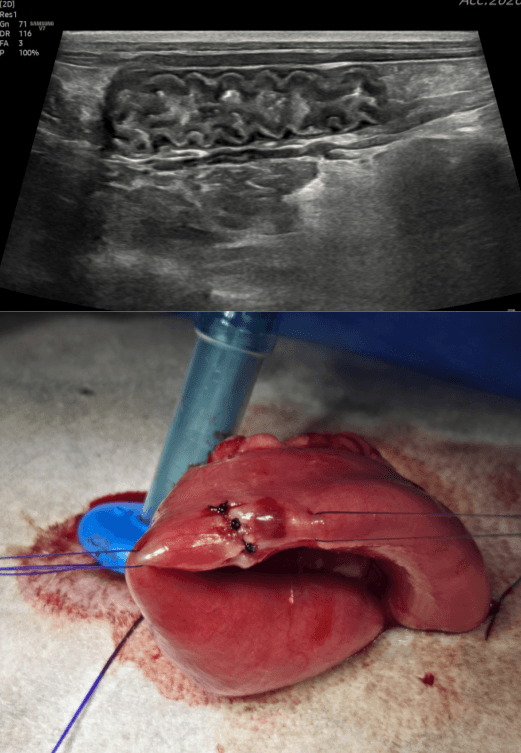

장벽의 층 구조, 림프절 부종, 종양 등을 정교하게 파악하여 침습도를 결정합니다.

개복 없이 위와 장 내부 점막을 직접 확인하고 IBD 확진을 위한 조직을 채취합니다.